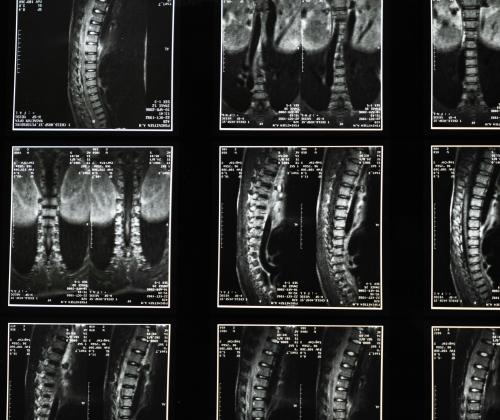

Scoliosis is a condition that causes the spine to curve abnormally from side to side, often creating a C-shaped or S-shaped curve.

In most cases, the condition is diagnosed in childhood or adolescence. Although the exact cause of scoliosis is not fully understood, it may be linked to factors like genetic predisposition.

Scoliosis is a spinal condition that affects approximately 2-3% of the U.S. population1. It is characterized by an abnormal side-to-side curvature of the spine, and researchers are actively investigating its various causes.

Scoliosis involves an abnormal curvature of the spine. According to the American Association of Neurological Surgeons, about 2-3% of the population in the United States has scoliosis.1